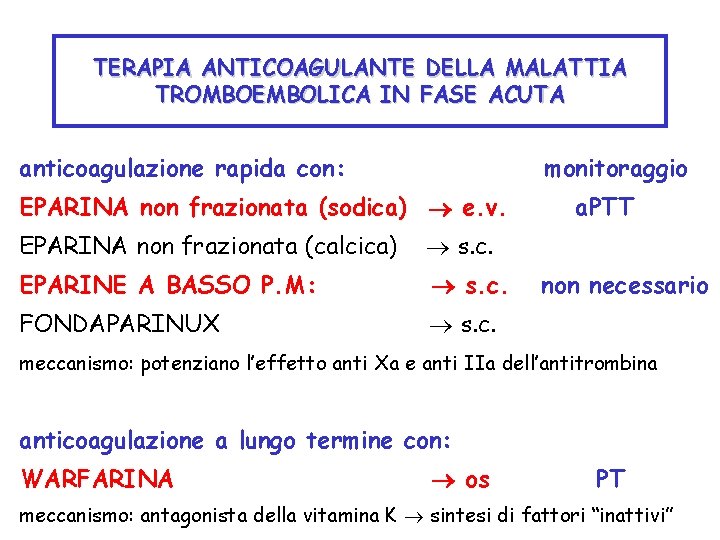

TERAPIA ANTICOAGULANTE DELLA MALATTIA TROMBOEMBOLICA IN FASE ACUTA anticoagulazione rapida con: monitoraggio EPARINA non frazionata (sodica) e. v. EPARINA non frazionata (calcica) s. c. EPARINE A BASSO P. M: s. c. FONDAPARINUX s. c. a. PTT non necessario meccanismo: potenziano l’effetto anti Xa e anti IIa dell’antitrombina anticoagulazione a lungo termine con: WARFARINA os PT meccanismo: antagonista della vitamina K sintesi di fattori “inattivi”